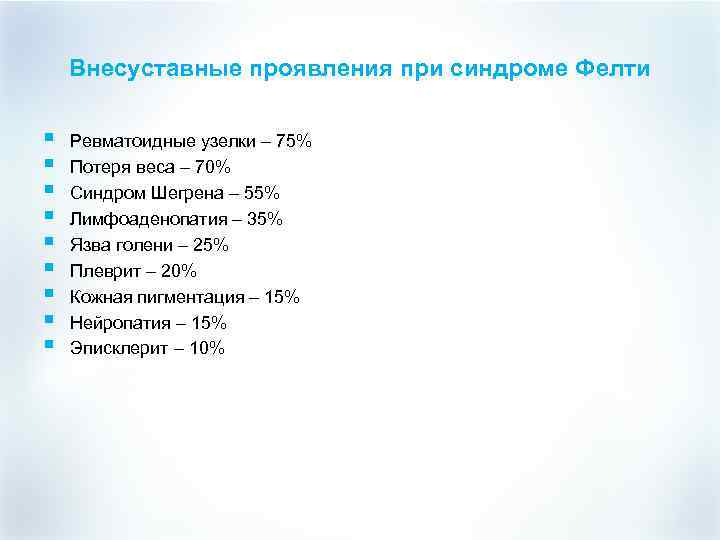

Внесуставные проявления при синдроме Фелти § § § § § Ревматоидные узелки – 75% Потеря веса – 70% Синдром Шегрена – 55% Лимфоаденопатия – 35% Язва голени – 25% Плеврит – 20% Кожная пигментация – 15% Нейропатия – 15% Эписклерит – 10%

Внесуставные проявления при синдроме Фелти § § § § § Ревматоидные узелки – 75% Потеря веса – 70% Синдром Шегрена – 55% Лимфоаденопатия – 35% Язва голени – 25% Плеврит – 20% Кожная пигментация – 15% Нейропатия – 15% Эписклерит – 10%